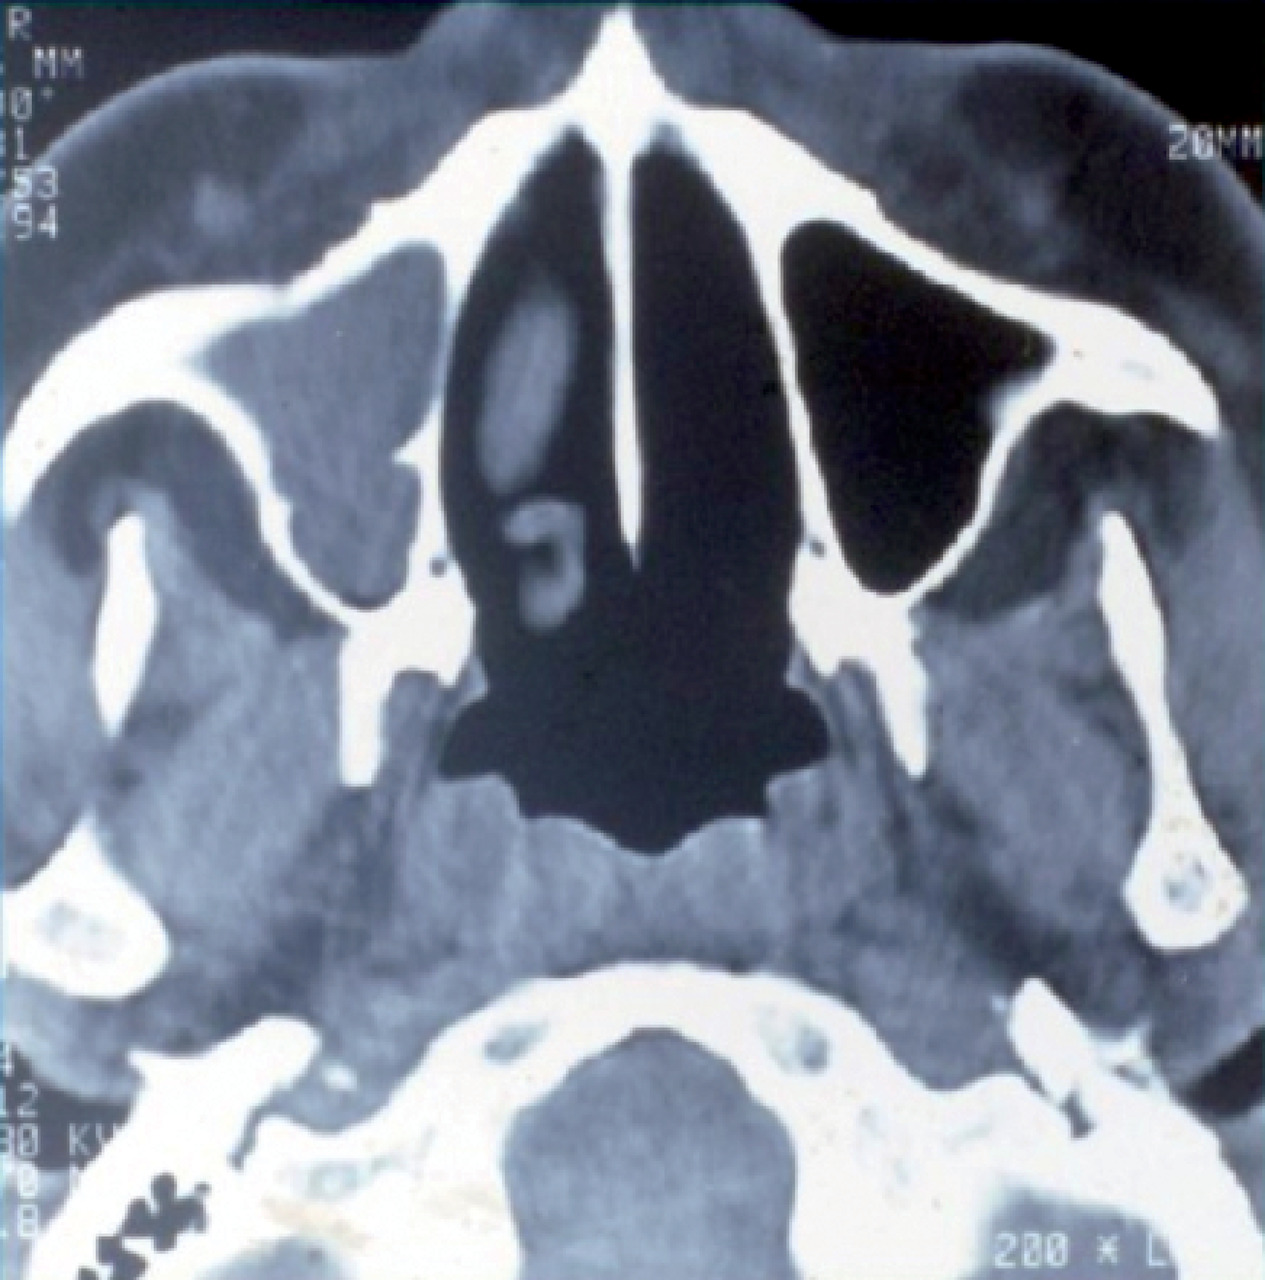

L’atteinte ORL se traduit par des manifestations initialement non spécifiques : rhinorrhée, épistaxis, sinusite ou otite séreuse, pouvant persister durant plusieurs semaines ou mois. La tomodensitométrie montre un comblement des sinus, qui peut évoluer vers une destruction osseuse (fig. 8).